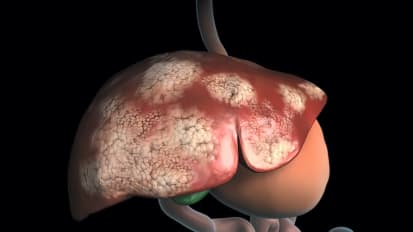

Liver cancer treatment costly for Medicare patients, UT Southwestern study finds News

Liver cancer treatment costly for Medicare patients, UT Southwestern study finds

Hepatocellular carcinoma (HCC), the most common type of liver cancer, can place a significant financial burden on patients, according to an analysis led by a researcher at UT Southwestern Medical Center.